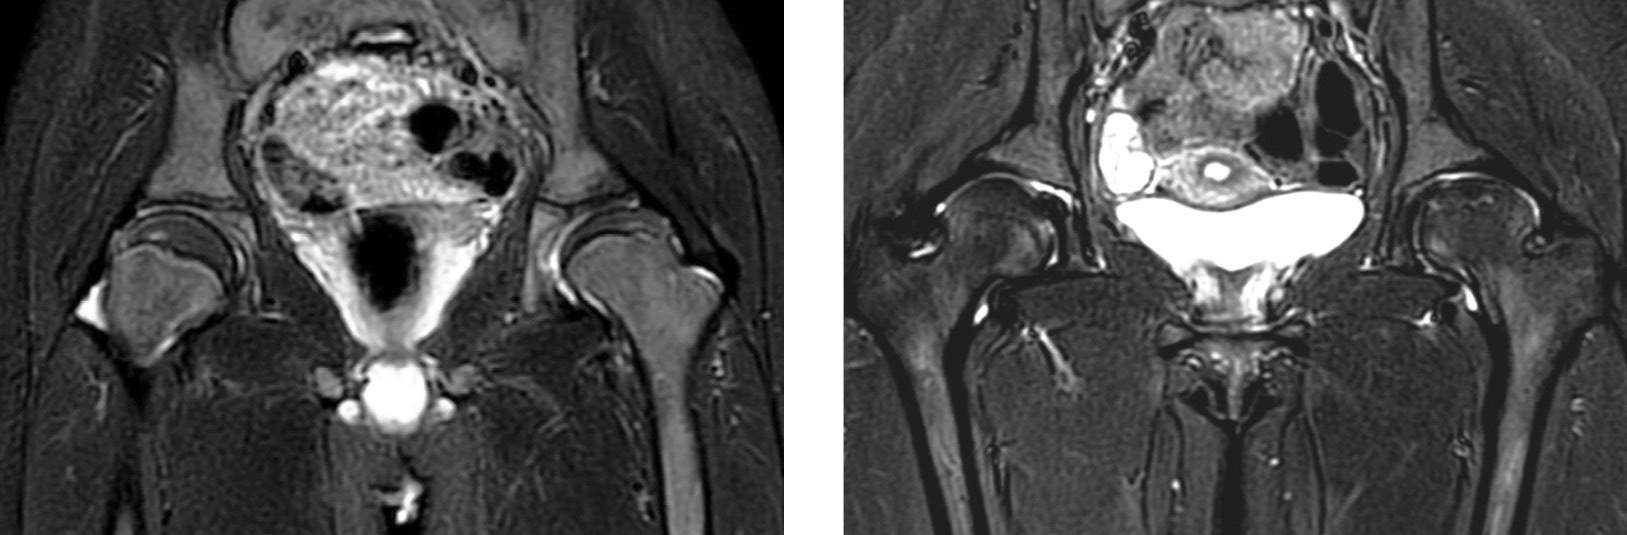

Рис. 4. Магнитно-резонансная томограмма: признаки неактивной стадии остеоартрита у двух детей с левосторонней болезнью Легга – Кальве – Пертеса на фоне применения бисфосфонатов, режим STIR